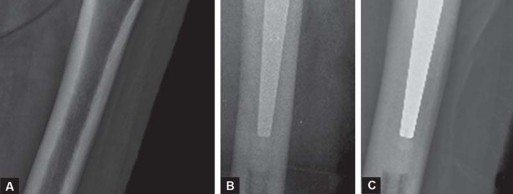

تقنية الإسمنت للفخذ، التي تُعد محور حديثنا، هي طريقة راسخة لتثبيت المكون الفخذي (الجزء الذي يتم إدخاله في عظم الفخذ) من المفصل الصناعي باستخدام إسمنت عظمي خاص. يضمن هذا الإسمنت استقرارًا فوريًا وقوة تحمل عالية، مما يجعله خيارًا ممتازًا للعديد من المرضى، وخاصة كبار السن وذوي العظام الضعيفة. ستكتشف في هذا الدليل لماذا تُعد هذه التقنية خيارًا موثوقًا به، وكيف يمكن أن تُحدث فرقًا حقيقيًا في حياتك.

- الدليل الشعاعي على التآكل الشديد: تُظهر الأشعة السينية تآكلًا كبيرًا في الغضروف، وتضيق